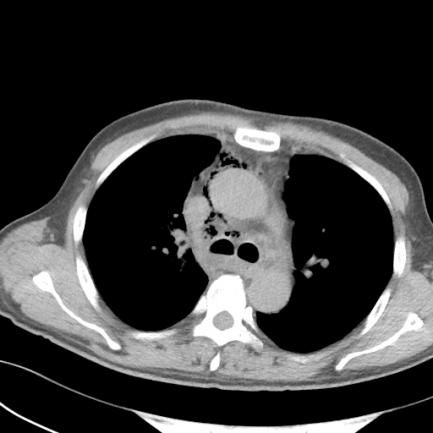

抢救室值班医师当机立断请耳鼻喉科急会诊,此时急诊检查结果回报:血常规:WBC(白细胞计数) 17.9*10^9/L;CT示纵隔、颈部及颌下软组织内积气影。

▲治疗前颈部(冠状位),胸部(轴位)

耳鼻喉科蒋锐主任会诊后考虑口腔颌面、颈部、纵隔多发感染导致的喉梗阻及感染性休克,局部穿刺得脓后更明确了诊断。